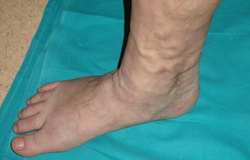

• Rezultat zdravljenja krčnih žil

Z lasersko operacijo so bile zvijugane, krčne žile odstranjene. Bolnica navaja izboljšanje v smislu utrujenih, težkih nog v večernih urah, kakor tudi glede otekanja in krčev.